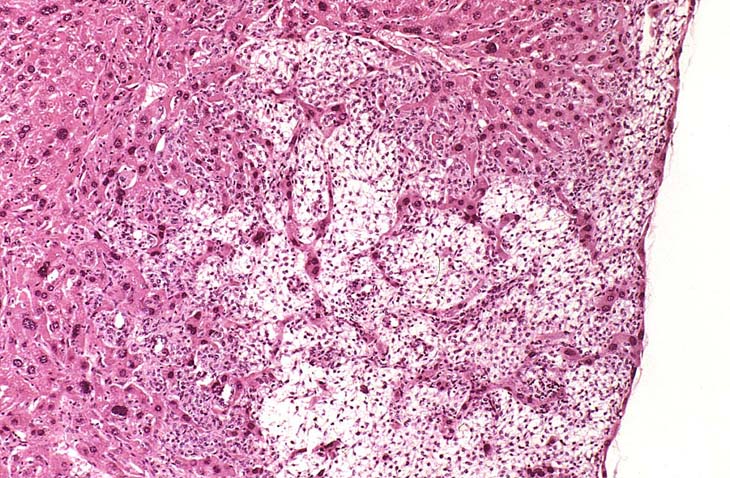

An Ito cell tumor that has replaced much of the normal hepatic parenchyma without distorting the normal contour of the liver; higher magnification shows fat-filled and stellate cells in the hepatic sinusoids.

The proliferating stellate cells have a myxomatous appearance in some areas and have caused atrophy of hepatic cords.